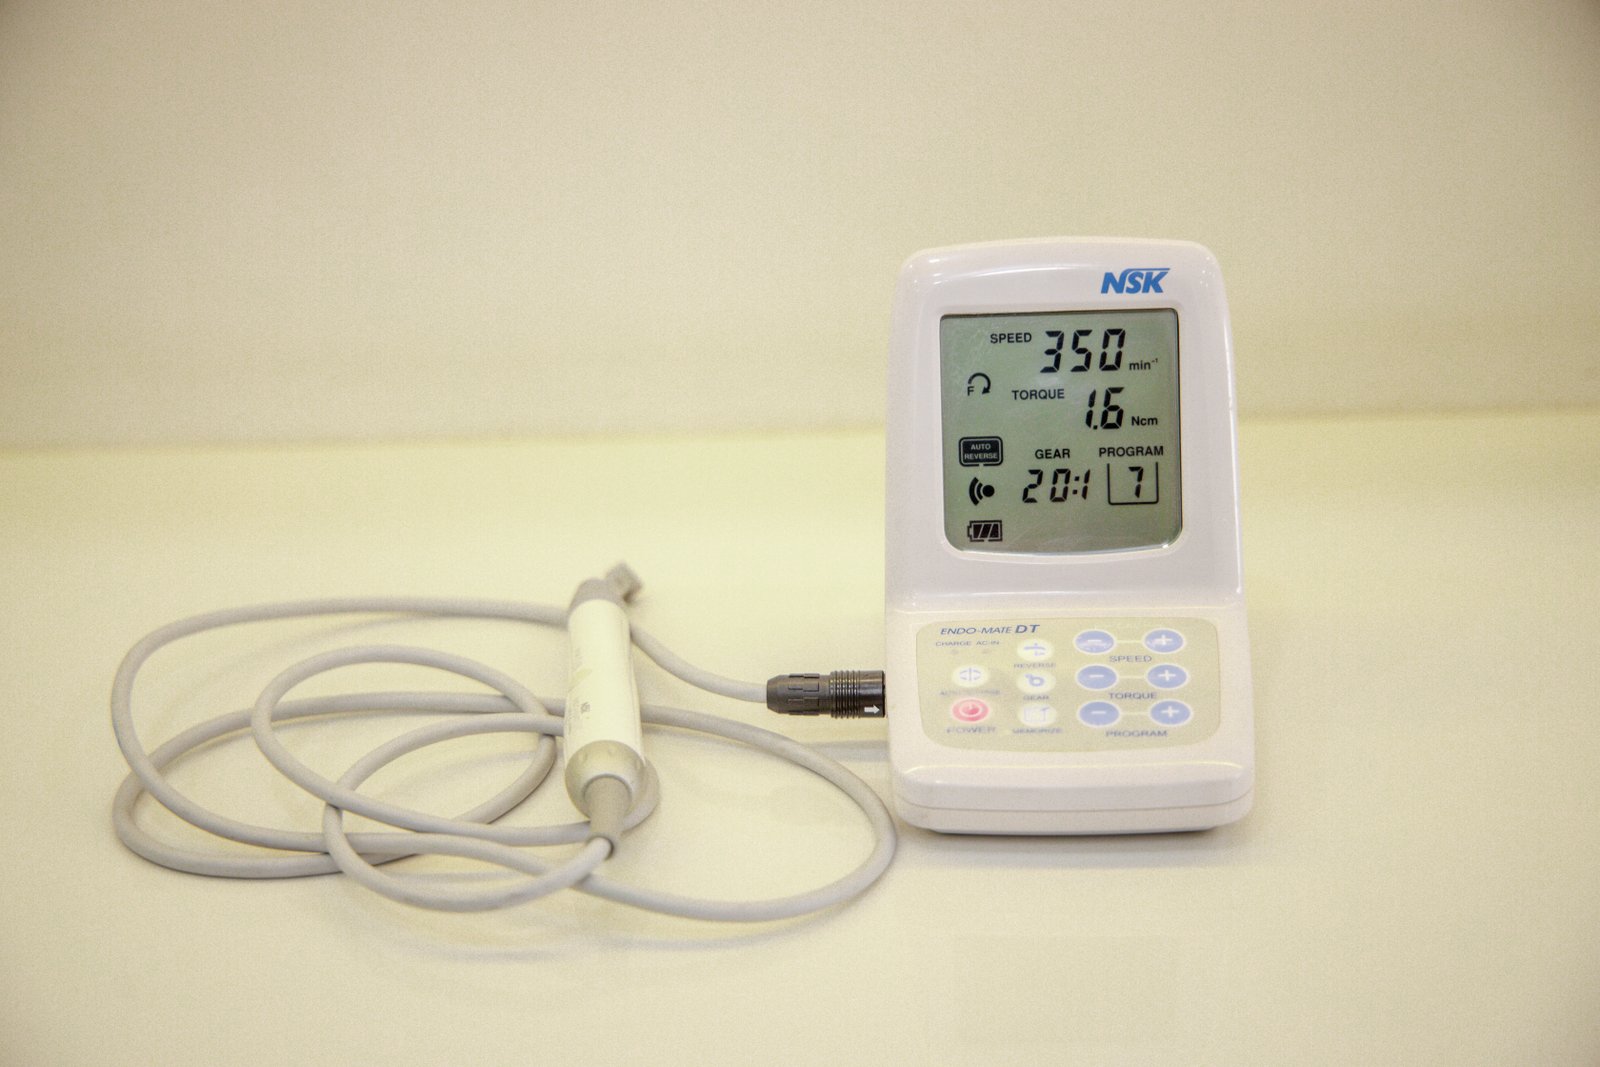

Specialized endodontic care to save infected teeth and relieve pain.

See every stage of our treatments with clear, step-by-step visuals that reflect our precision and care.